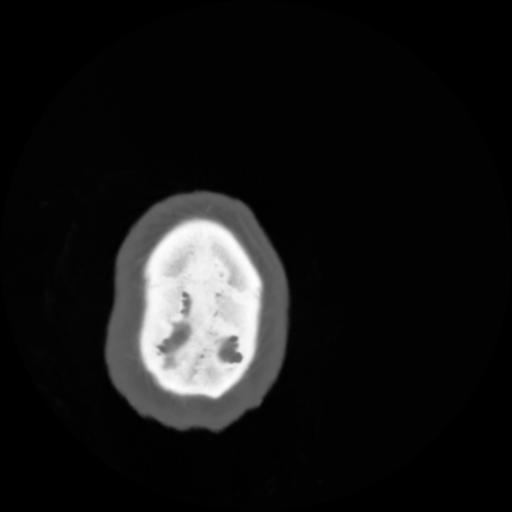

4 CEREBRO,,Vol,0.5,CEREBRO,,